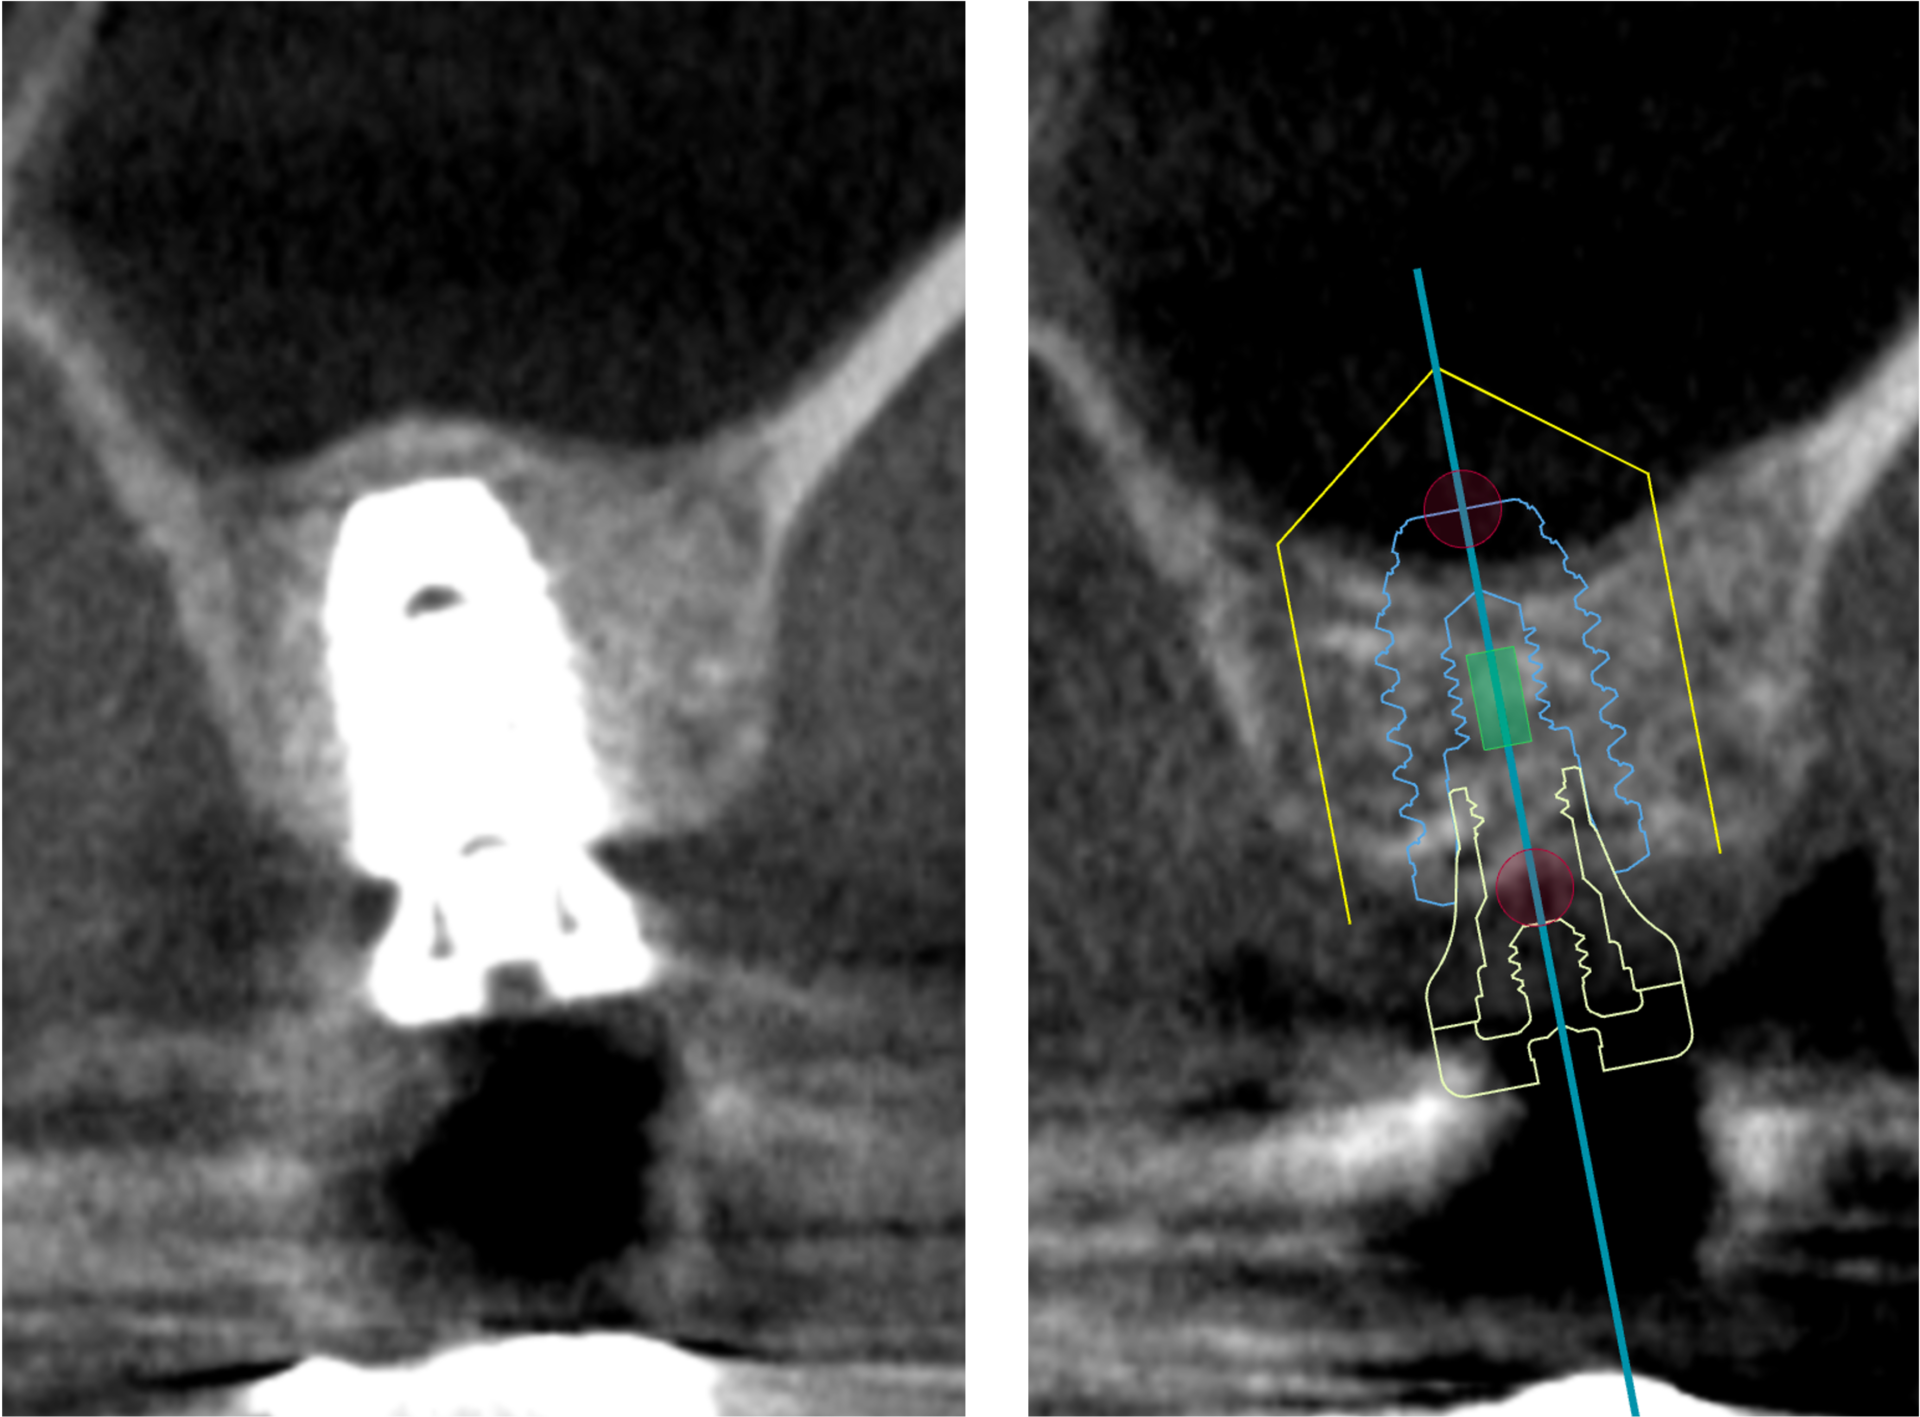

本日は、上顎の骨が少ない方にインプラント治療を行った治療を紹介させていただきます こちらの患者様は、上顎の大臼歯に欠損がありインプラント治療を希望されていらっしゃいましたしかしながら一般的な長さのインプラントを埋め込むには上顎の骨の高さが不足しており、インプラントの先端1/3が上顎洞(鼻の横の空洞)に突き出してしまうという診断となりました このような現存する …